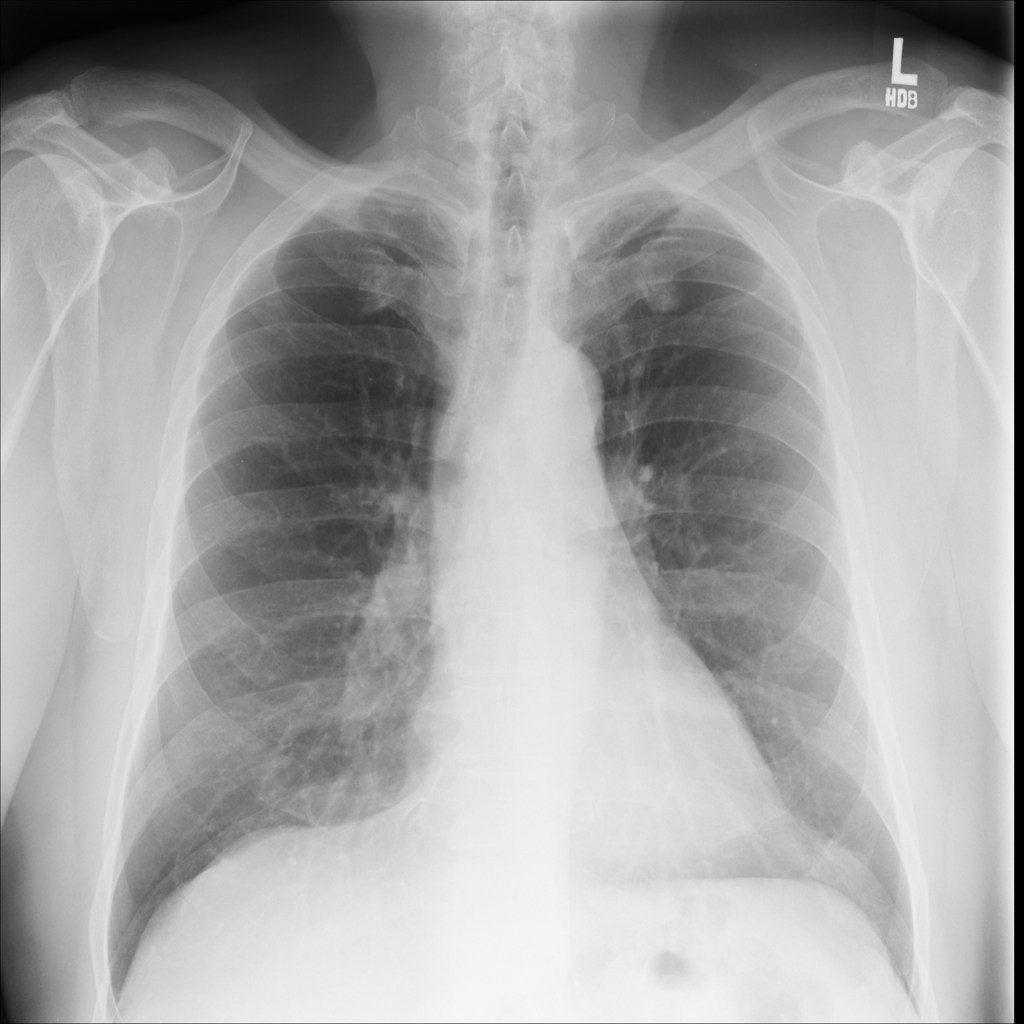

PAT-B0DB · IMG-003Emphysema

PAT-B0DB · IMG-003

PA